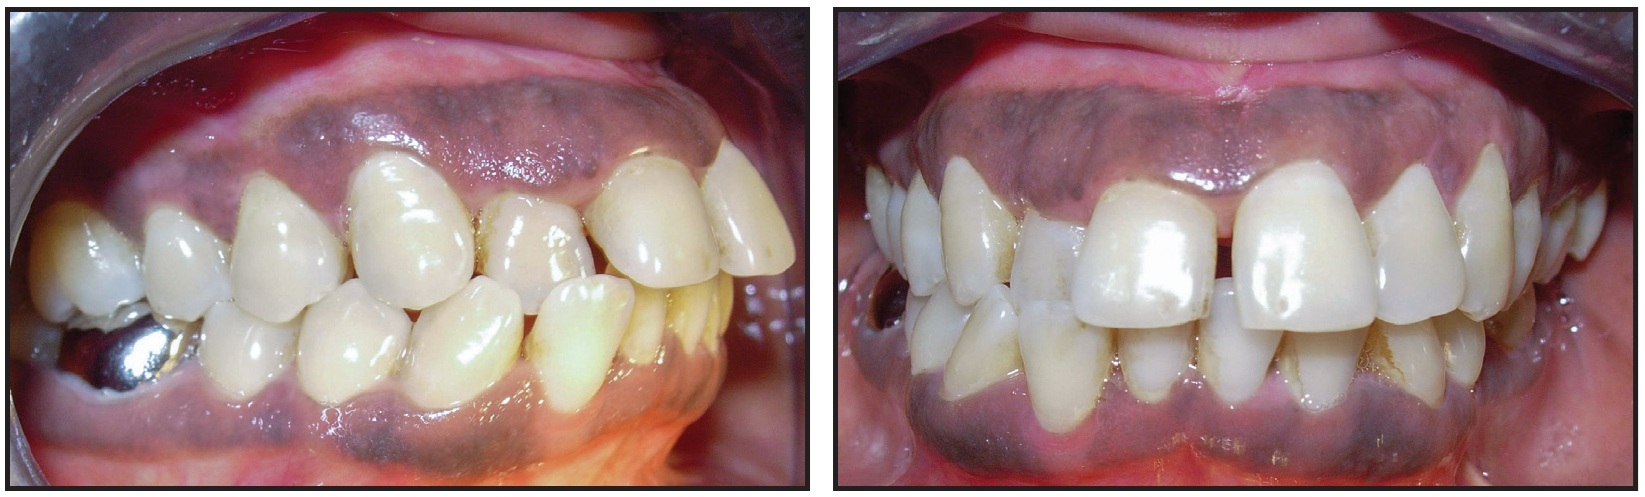

A 40-year-old male was referred by his dentist because of esthetic and functional problems. Intraoral examination showed lower anterior crowding accompanied by tartar deposits and a crossbite of the upper right lateral incisor with the lower right lateral incisor and canine (Fig. 1).

Fig. 1 40-year-old male patient with lower anterior crowding and crossbite, deviation of mandibular midline, and inflammatory gingival recession of lower right lateral incisor before treatment.

The lower right lateral incisor exhibited Class II mobility and inflammatory gingival recession on the labial side. The patient had a Class I occlusal relationship with a 4mm overjet and a 2.5mm overbite; the mandibular midline was deviated to the right.

Functional examination revealed an abnormality in the path of closure, resulting in deviation of the mandible to the right. A masticatory dysfunction was indicated by the occlusal trauma to the lower right lateral incisor, but the panoramic radiograph showed no evidence of root lesions.